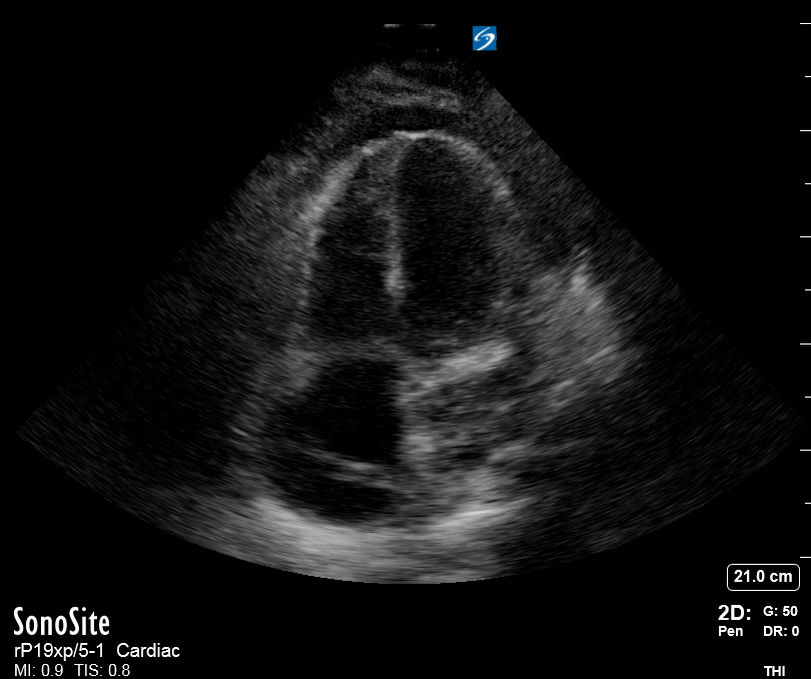

Effusion: is there a pericardial or pleural effusion?

Pericardial effusion is a continuum and can potentially evolve into haemodynamic collapse. Tamponade physiology is detectable earlier with ultrasound than with traditional physical examination, and it has been demonstrated that PoCUS improves mortality in penetrating cardiac trauma. Timely and accurate diagnosis is, therefore, vital.

THE VIEWS

The subxiphoid view is the most reliable for detecting pericardial effusion. Still, it is ideal to obtain different views not to miss a focal effusion as small amounts of fluid can lead to tamponade physiology. Tamponade does not link strictly to the size of the effusion, but correlates more with the speed of onset, causes, and haemodynamic effects.

PITFALLS & PLEURAL EFFUSIONS

A common error is to confuse a pericardial fat pad with effusion. Fatty tissue has a heterogeneous echotexture, moving in coordination with the myocardium, and it cannot be tracked around the heart, especially posteriorly and to the apex. Another pitfall is misinterpreting a pleural effusion as a pericardial effusion. However, they can be differentiated by their relationship to the descending aorta. Pericardial effusion may be seen between the aorta and the LV free wall, whereas pleural effusions are posterior to the descending aorta. Lastly, other causes, namely hypovolaemia and large pleural effusions, can cause RA and RV collapse.

CARDIAC TAMPONADE

Progressively rising pressure translates into evolving tamponade, and this accompanies a series of ultrasound findings:

Initially, the RA collapses during ventricular systole (closed AV valves).

Followed by RV collapse in ventricular diastole (open AV valves).

Ultimately leading to LV collapse.

In addition, the presence of a non-collapsible, plethoric IVC is one of the most sensitive signs of tamponade, and a finding easy to visualise. Conversely, a pericardial effusion in a haemodynamically stable patient with a collapsible IVC is unlikely to represent tamponade.

Chamber collapse can be assessed in M-mode, where the collapsing RV is seen as a notch that takes place right after the mitral valve opening and before its closure (during diastole).